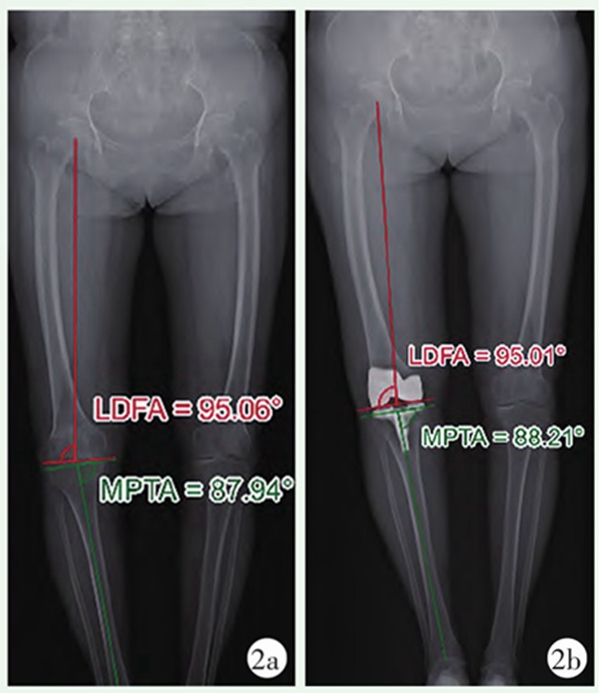

图1 MA-TKA患者双下肢站立位全长X线片

1a:术前X线片;1b:术后X线片患者股骨及胫骨排列被矫正至90°中立位;LDFA:股骨远端外侧角;MPTA:胫骨近端内侧角

1973年,Freeman等提出垂直股骨胫骨机械轴截骨的概念,不久后,Insall等强调了膝关节置换术间隙平衡的重要性,自此,机械力学对线便成为膝关节置换的“金标准”。机械力学对线强调垂直于股骨及胫骨各自的机械轴进行截骨,由此得到一个中性对线的膝关节,关节内外侧间室的压力均匀分布,从而将假体磨损及松动的风险降至最低(图1)。偏离中性机械对线,可造成聚乙烯衬垫磨损加速、骨溶解及假体下沉的风险,从而影响假体的使用寿命。临床证据证明该技术能够保证良好的假体远期存活率和可接受的功能活动。此后人们逐渐形成共识:TKA术后下肢机械轴偏离值应控制在±3°范围内(即髋-膝-踝角应小于±3°),以防止中长期的假体失败风险。但越来越多的证据表明,该对线方法带来的患者术后满意度并不高。来自英格兰和威尔士国家联合登记处的数据表明,近20%的患者对自己术后功能不满意。然而,无论是使用技术辅助手段以提高置入物的精确度,还是新的置入物设计,都无法进一步提高患者的满意率。研究显示MA技术存在先天的局限性:它通过改变固有解剖结构、生理性韧带平衡和运动学特点来制造的非生理性膝关节,改变了软组织原本的张力、打破了原有的运动平衡,从而导致患者功能及症状的改善程度均不高。